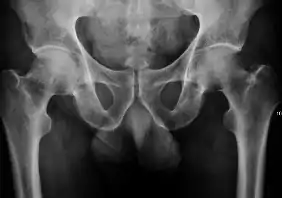

Medical imaging

Projectional radiography ("X-ray") is the first imaging technique of choice in hip pain, not only in older people with suspected osteoarthritis but also in young people without any such suspicion. In this case plain radiography allows categorization as normal hip or dysplastic hip, or with impingement signs, pincer, cam, or a combination of both.[1]

X-Ray

Projectional radiography ("X-ray") is currently useful not only in older people in whom osteoarthritis of the hip is suspected but also in younger people without osteoarthritis, who are being evaluated for femoroacetabular impingement (FAI) or hip dysplasia.[1]

Plain radiography allows us to categorize the hip as normal or dysplastic or with impingement signs (pincer, cam, or a combination of both). Besides these, pathologic processes like osteoarthritis, inflammatory diseases, infection, or tumors can also be identified (Figure 1).[1]

Figure 1.

Radiography in normal hip

X-ray in pincer impingement type of hip dysplasia

X-ray of cam

Hip in osteoarthritis

Septic arthritis

X-ray in pediatrics